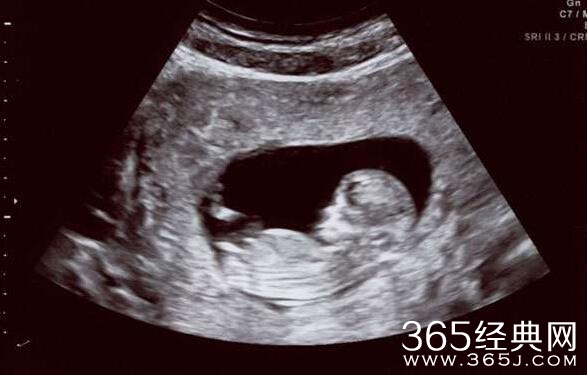

在她怀孕时,莉娜希望自己能生下一名女婴,但是当她怀孕五个月的时候,医生告诉她她怀有一个男孩,接着,她的灾难接踵而来。